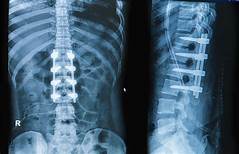

Shree Datta Hospital comprises of a multidisciplinary team that offers a holistic approach in the management of Spinal problems. We aim to provide safe, high quality, cost-effective and state of art, operative and non-operative management of spinal disorders. Multidisciplinary consultation ensures that every patient receives a complete assessment and even the most complex spinal problems will be effectively handled.

ADVANCED SPINE PROCEDURES

Deformity correction is the surgical adjustment or modification of bone that grows incorrectly as the result of a disease or condition.